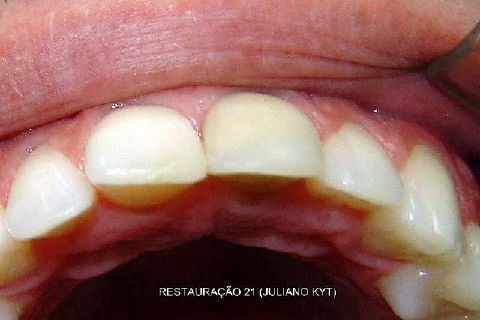

Bom, aí procurou o colega Dr. Juliano Kyt, que gentilmente salvou o que restou...

Nos falamos por telefone e eu lhe expliquei o histórico todo do dente, enviei-lhe o CC por e-mail e lhe pedi que fizesse um trabalho conservador, que oportunamente eu faria uma faceta ou CT em porcelana.

O que está escrito ao lado das fotos são palavras do colega Dr. Juliano Kyt. Ele autorizou-me postar as fotos aqui, inclusive convidei-o para participar do iDent.

Bem, como falei no 1º capítulo, temos aqui o 2º e ainda termos o 3º, que espero que seja o último!

Mais uma coisa... o dono do dente é MEU PRIMOGÊNITO!!! Afffffff.............